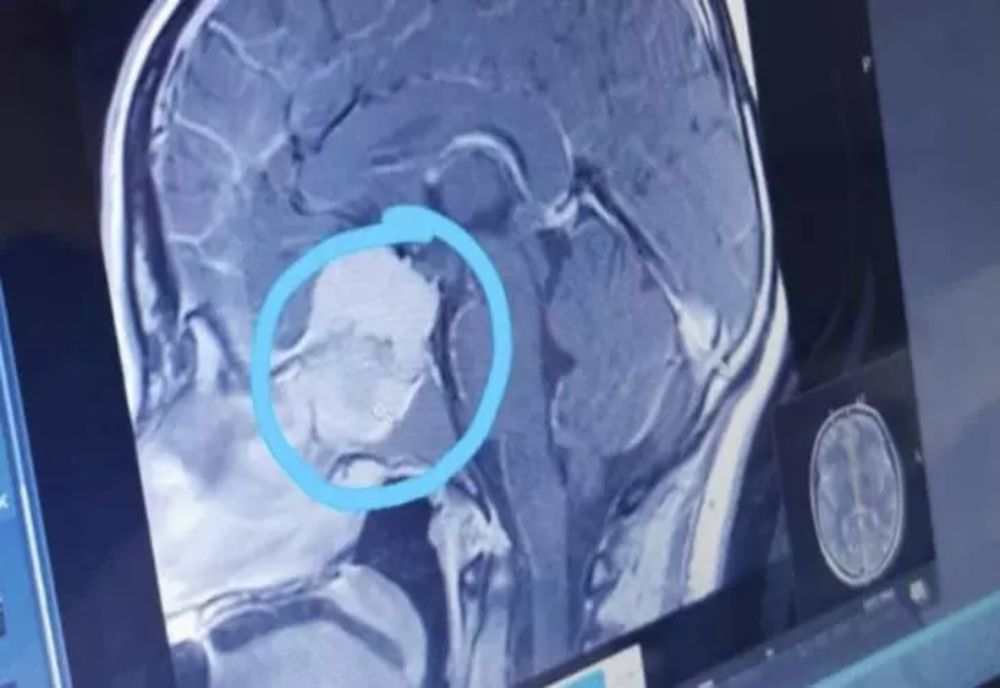

14 mar. 2023, 08:07ActualitatePersoanele cu această grupă de sânge au cel mai mare risc de accident vascular cerebral